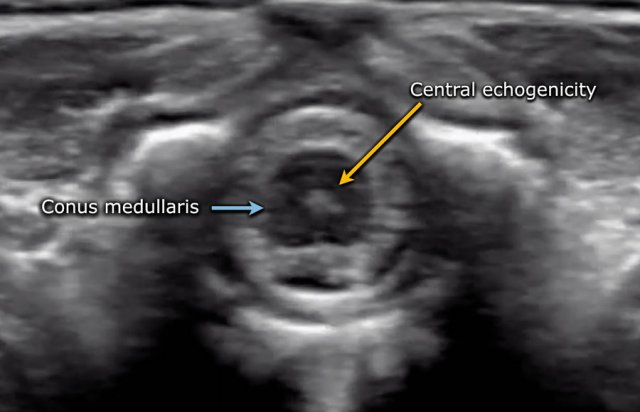

The spinal cord is depicted as a very hypoechoic structure with a central echogenicity.

This central echogenicity is supposed to represent the interface between the anterior commissure and the median anterior fissure, and not the central canal.

Axial image of the spinal cord with central echogenicity.

Axial image of the cauda equina.

The lower end of the cord is thickened, which is the lumbar intumescence.

The cord tapers in a sharp cone (blue arrow).

The cauda equina is seen as a bunch of moving strands.

If the baby is lying in the decubitus position, the strands will gravitate to the dependent posterior side.

If the baby is examined in the prone position with a pillow under the abdomen, the stands will move ventrally.